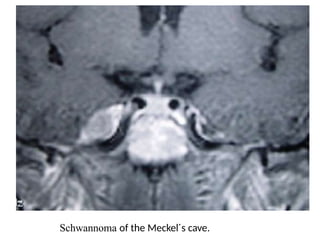

Schwannoma of the Meckel´s cave.

Schwannoma of theMeckel´s cave.